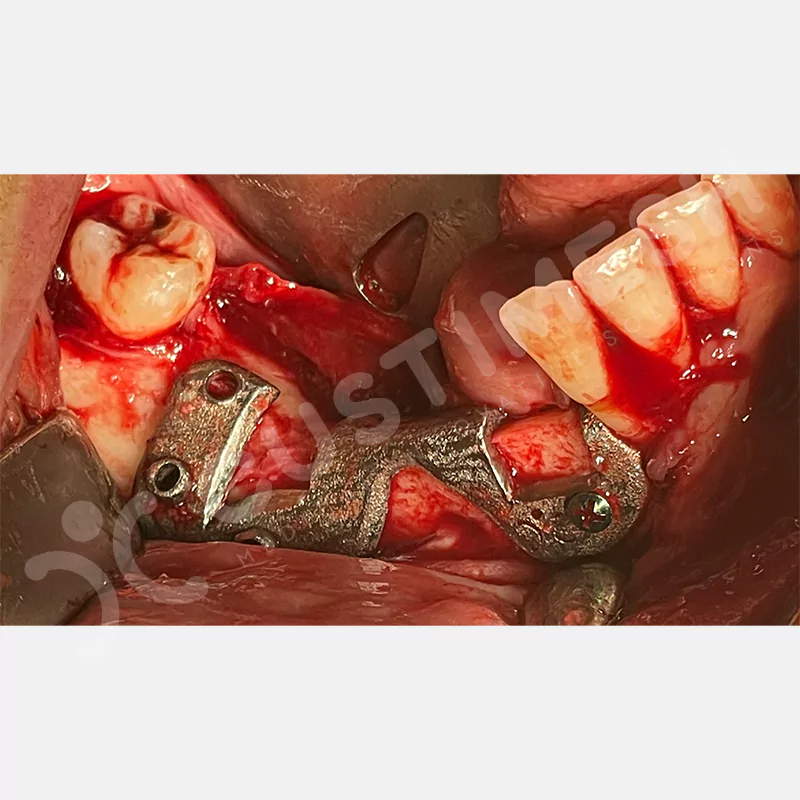

Modern diş hekimliğinde, çene gelişimini tamamlamamış veya ciddi kemik kaybı yaşayan hastalar için kişiye özel titanyum implantlar ile çözüm bulunmaktadır. CAD/CAM teknolojisi ve lazer sinterleme yöntemiyle üretilen bu implantlar, hastanın bireysel anatomik yapısına tam uyum sağlayarak geleneksel implantların uygulanamadığı vakalarda mükemmel bir alternatif oluşturmaktadır. Özellikle ileri derecede kemik kaybı olan hastalar için geliştirilen subperiosteal implantlar, periostun altına yerleştirilerek minimal invaziv bir yaklaşım sunarken, bilgisayarlı tomografi verileri ve sonlu eleman analizleriyle optimize edilmiş tasarımları sayesinde hem estetik hem de fonksiyonel sonuçlar garanti etmektedir. Bu yenilikçi teknoloji, tek seansta implant ve protez uygulamasına imkan vererek hastaların aynı gün doğal gülüşlerine kavuşmalarını sağlarken, kemik greftleme gibi ek işlem ihtiyacını ortadan kaldırarak cerrahi süreci büyük ölçüde kolaylaştırmaktadır. Kişiye özel tasarımı ve üstün biyouyumluluğu sayesinde, daha önce tedavisi mümkün görülmeyen kompleks vakalarda bile başarılı sonuçlar sunan bu implantlar, modern diş hekimliğinde yeni bir çağ açarak hastaların yaşam kalitesini artırmayı hedeflemektedir.

VAKA 1